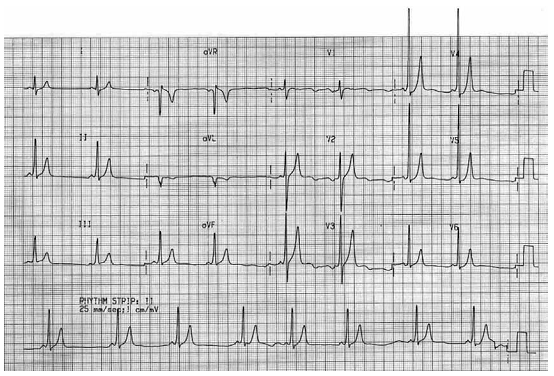

Homem, 22 anos, é trazido a serviço de emergência com taquicardia instável de QRS largo. Realizada cardioversão elétrica sincronizada. No gráfico, mostra-se o traçado de eletrocardiograma realizado após a cardioversão.

O diagnóstico provável é: